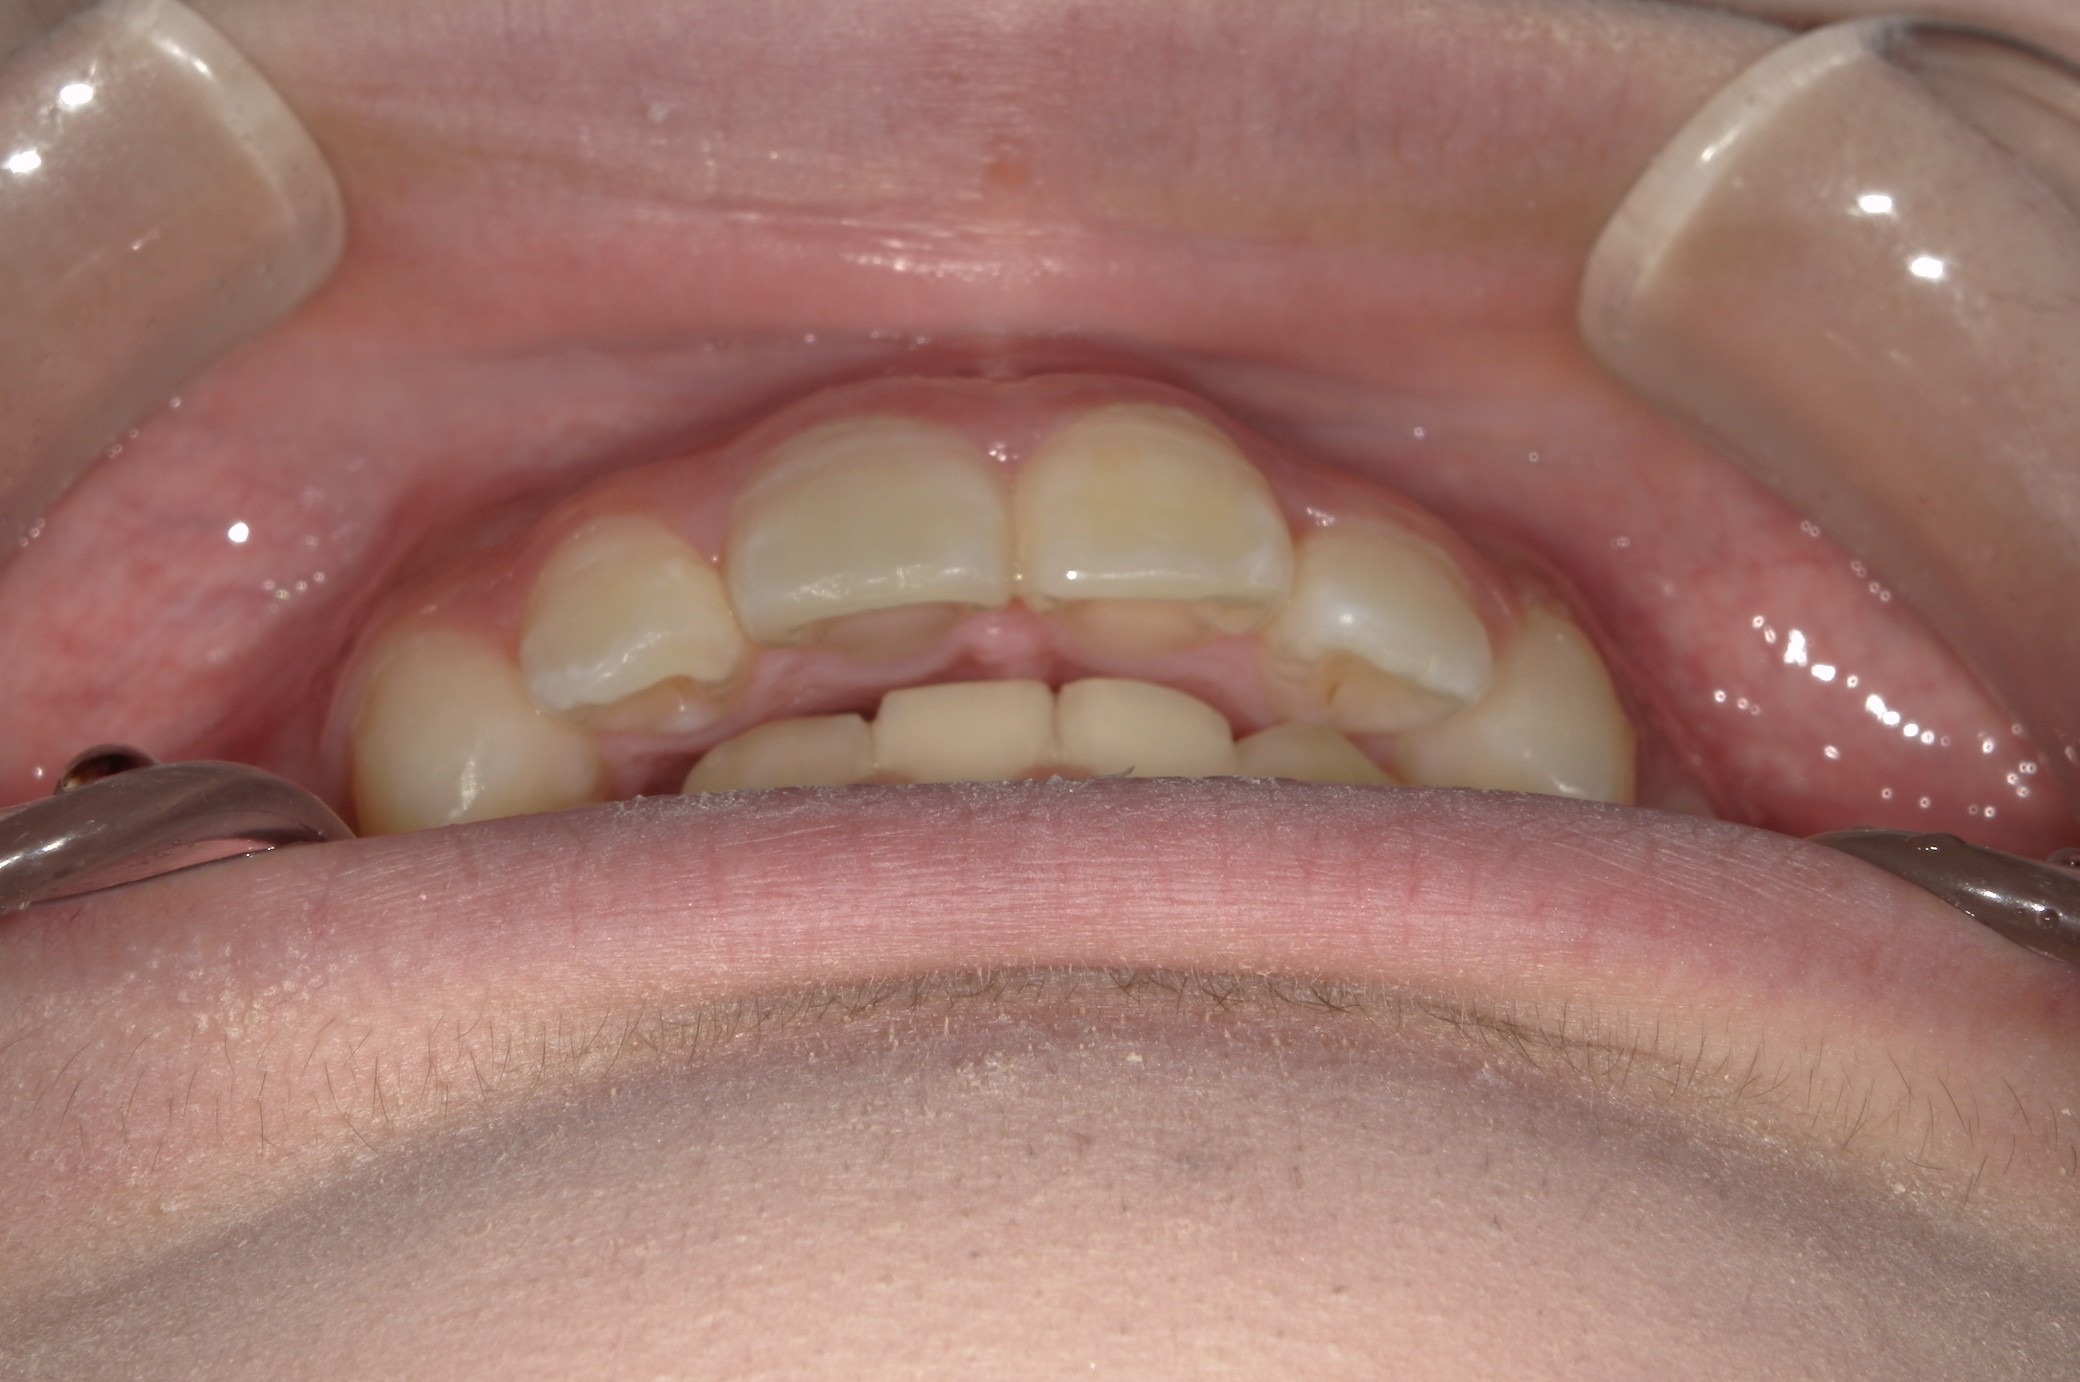

矯正術前:正面

矯正術前:オーバージェット